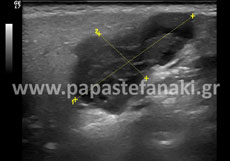

Υπέρηχοι θυρεοειδούς

Προετοιμασία ασθενούς Δεν απαιτείται.

Υπέρηχοι τραχήλου

Υπέρηχοι μαλακών μορίων

Υπέρηχοι μαστών

Προετοιμασία ασθενούς Δεν απαιτείται. Πρέπει να προσκομίσετε προηγούμενη μαστογραφία ή/και υπερήχους μαστών. Είναι προτιμότερο η εξέταση να γίνεται στην μέση του κύκλου.